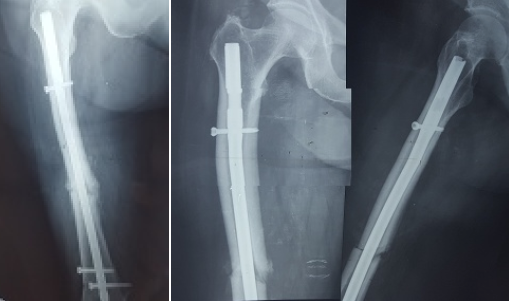

According to the newest guidelines of the ASBMR (American Society of Bone and Mineral Research), the patient underwent intramedullary nailing of the right femur and was instructed to discontinue bisphosphonate along with non-weight bearing of the left lower extremity [17-19]. Although a bone scan was conducted for further investigation of the incomplete fracture and the presence of other imperfect fracture sites, no new lesions were found (Figures 2 and 3). After 6 weeks, there was a clinical improvement in the left femur and radiographic appearance of callus, thus excluding the prophylactic intramedullary nailing of the left femur. The union of both fractures developed normally both for the right femur which was treated with intramedullary nailing and the left femur where conservative treatment was selected. The union of the right femur was not affected by the fact that the distal locking screw was not centered in the nail hole. The radiographic monitoring of the bone healing was conducted at 3, 6 and 12 months after the first treatment took place (Figures 4 and 5).

Figure 4. Postoperative radiographs taken two and six months after surgery. The left one shows one AP view of the femoral shaft with the IM nail. The other two shows one AP and P view of the upper one half of the femur